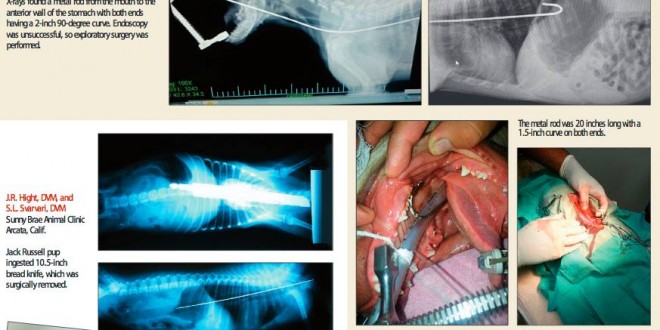

收好你的襪子、黃色小鴨跟燈泡!不然它們會出現在你家毛小孩胃裡!